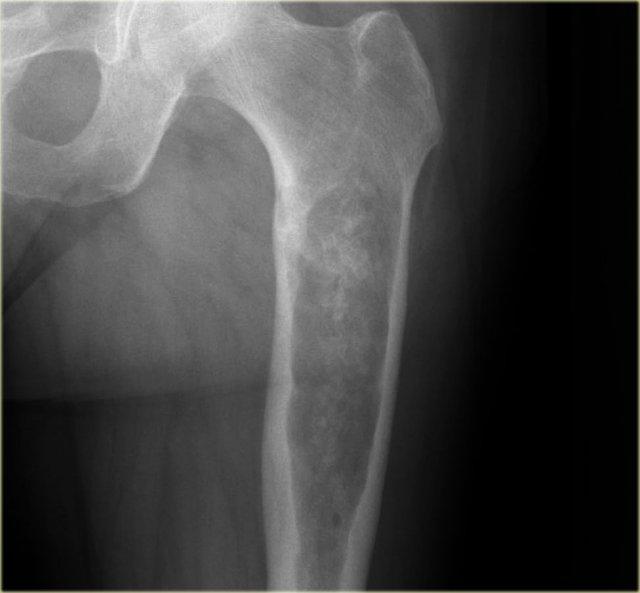

Phim X-quang thường bên trái cho thấy tổn thương tiêu xương không rõ ranh giới ở thân xương cánh tay.

Lưu ý hiện tượng xâm lấn dạng đường hầm qua vỏ xương (mũi tên đỏ).

Trên hình MR, lưu ý các bất thường dạng tuyến tính trong vỏ xương và khối mô mềm bao quanh theo chu vi.

Chẩn đoán phân biệt (tùy theo độ tuổi): Sarcoma Ewing, viêm tủy xương và u lympho xương.

Sinh thiết xác nhận u lympho không Hodgkin